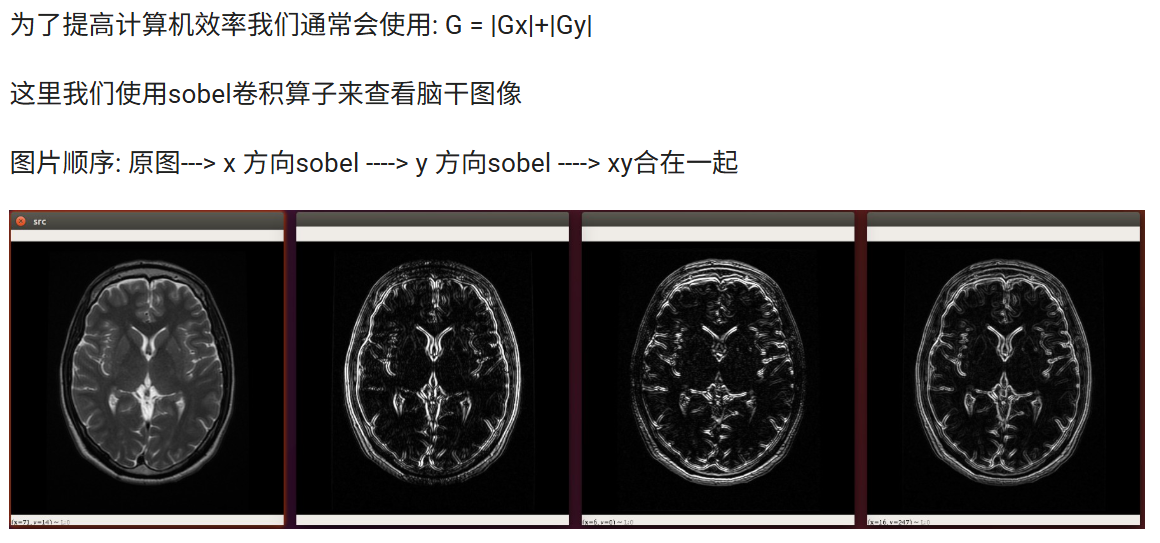

Sobel算子是像素图像边缘检测中最重要的算子之一,在机器学习、数字媒体、计算机视觉等信息科技领域起着举足轻重的作用。在技术上,它是一个离散的一阶差分算子,用来计算图像亮度函数的一阶梯度之近似值。在图像的任何一点使用此算子,将会产生该点对应的梯度矢量

import cv2 as cvimg = cv.imread("./assets/brain.jpg",cv.IMREAD_GRAYSCALE)

cv.imshow("src",img)# sobel算子 参数1:图像, 参数2:图像的深度 -1表示和原图相同, 参数3: x方向求导的阶数 参数4: y方向求导的阶数

x_sobel = cv.Sobel(img, cv.CV_32F, 1, 0)

# 将图像转成8位int

x_sobel = cv.convertScaleAbs(x_sobel)cv.imshow("x sobel",x_sobel)# sobel算子

y_sobel = cv.Sobel(img, cv.CV_16S, 0, 1)

# 将图像转成8位int

y_sobel = cv.convertScaleAbs(y_sobel)

cv.imshow("y_sobel",y_sobel)# 将x,y方向的内容叠加起来

x_y_sobel = cv.addWeighted(x_sobel, 0.5, y_sobel, 0.5,0)

cv.imshow("x,y sobel",x_y_sobel)cv.waitKey(0)